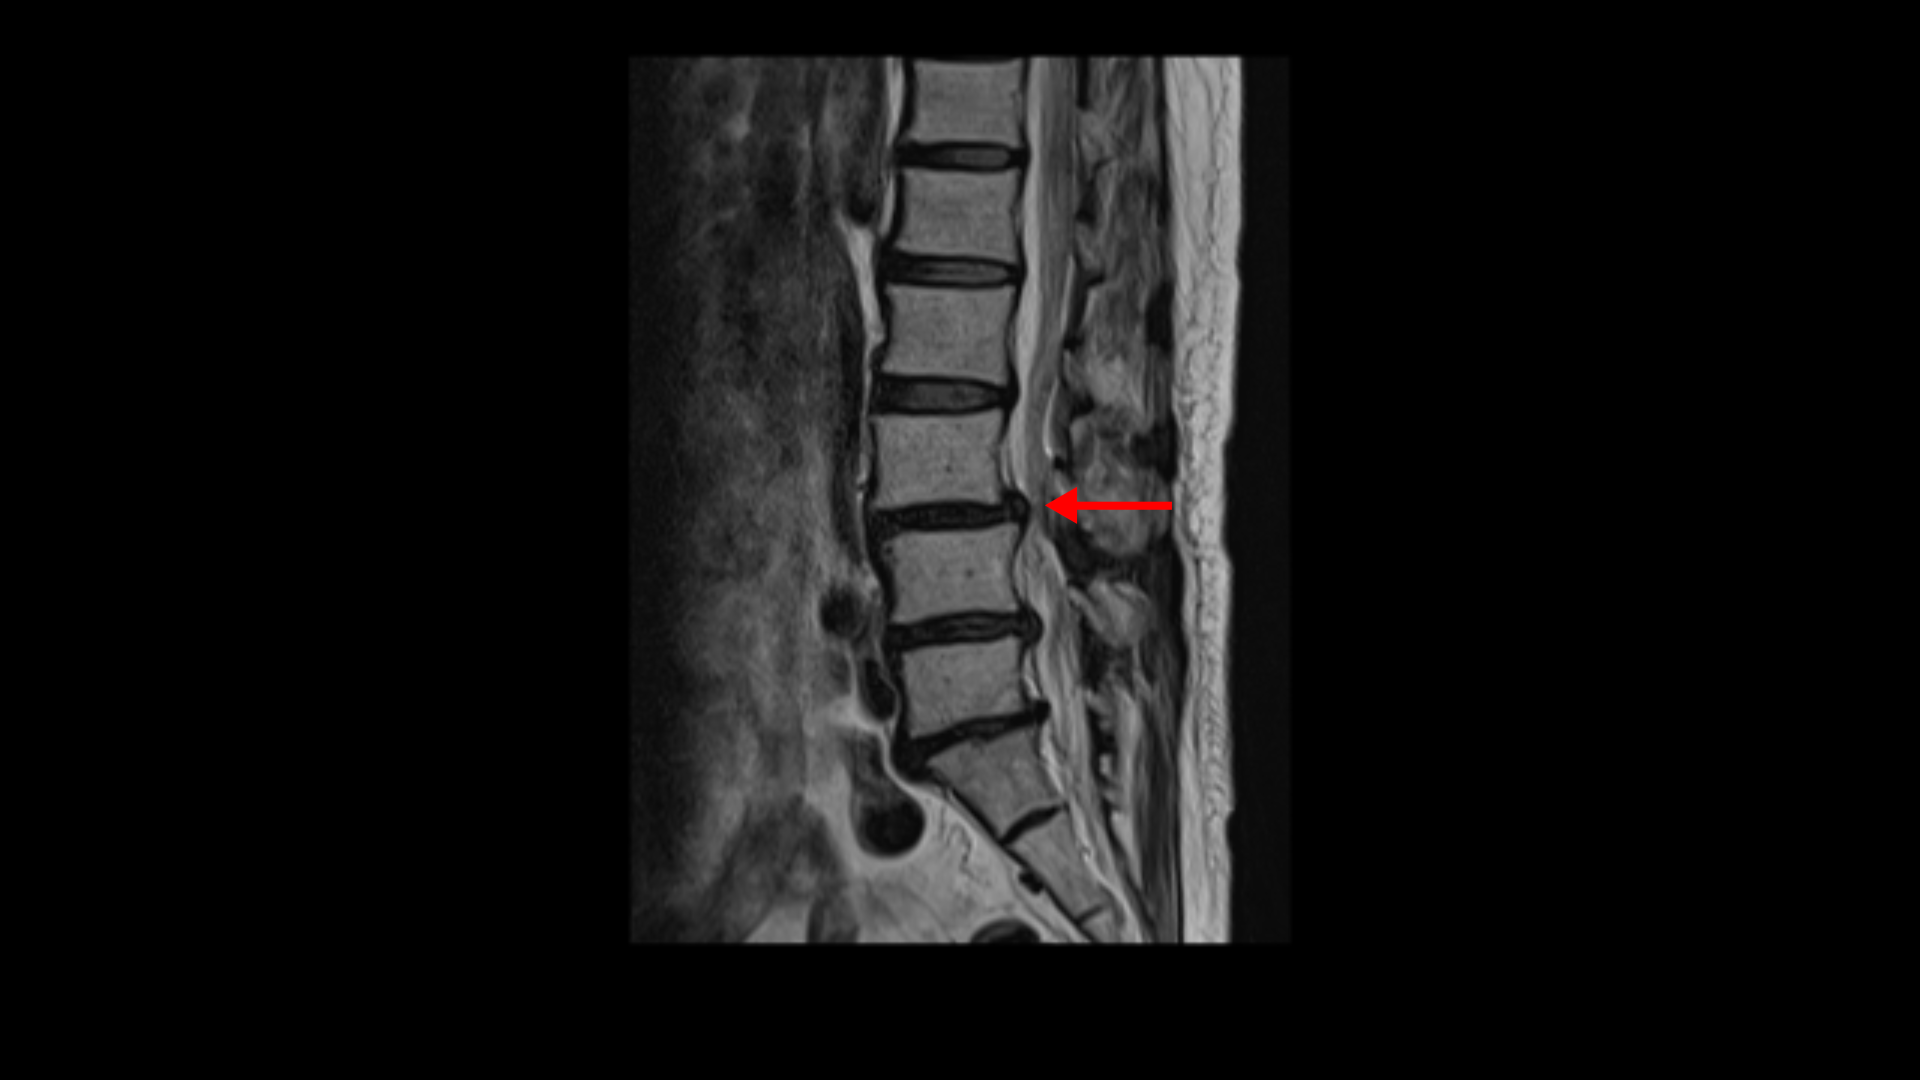

이분 MRI를 보면 3마디에 퇴행성디스크가 밀려 나와 있습니다.

또 3번 4번에는 척추전방전위증이 있습니다.

이 전방전위증 때문에 척추관에 중심성 협착도 있습니다.

4번 5번 디스크가 중앙에서 우측으로 약간 밀려 나와있고

>또 5번 1번에서는 신경이 빠져나가는 오른쪽 추간공이 약간 좁아져 있습니다.

이런 문제들 때문에 오른쪽 엉치부터 발가락까지 방사통이 있을 가능성이 있습니다. 하지만 어떤 마디가 정확한 통증의 원인인지 알기 어렵고 여러 마디가 안 좋기 때문에 이 환자분의 말씀을 들어봐도 전체적으로 여러마디 다 나사를 박자는 얘기를 들은 걸로 보입니다. 이렇게 여러 마디에 나사를 박는 유합술을 해놓으면 시간이 흘러 위나 아래에 문제가 생길 가능성도 커지고 환자분도 50대 초반의 젊은 나이라 대학병원의 교수님도 수술하기엔 너무 젊은 데라고 여러 번 말씀하셨다고 합니다. 그런데 신경 주사를 그토록 여러 번 오랜 시간 맞았는데도 환자가 심하게 아프면 수술 외에는 뾰족한 다른 방법이 없는 것이죠.

그런데 이분 허리 MRI를 자세히 보면 딱히 신경이 아주 극심하게 눌린 곳도 없습니다.

신경이 조금 눌릴 수는 있어도 심각해 보이지는 않습니다.

신경구멍이 지나가는 길이 여러 가지 퇴행성 변화로 조금씩은 좁아져 있지만 굳이 수술로 특히 여러 마디의 나사를 박는 수술까지 해가며 신경압박을 해소해야 할 정도의 심한 신경눌림은 보이지 않는 겁니다.